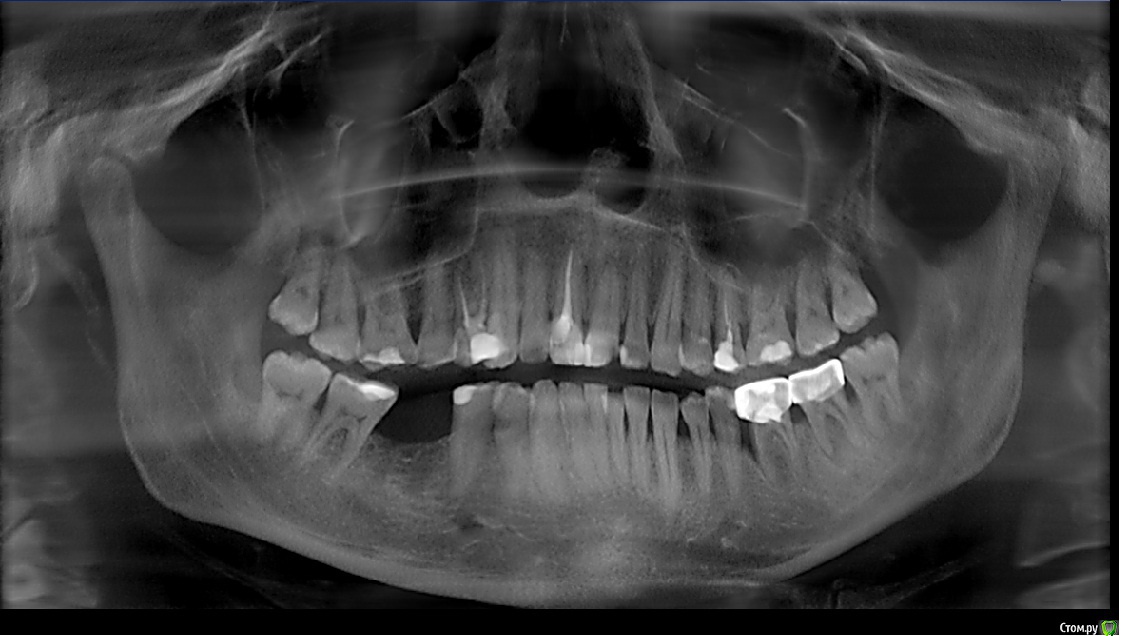

Sampson Опубликовано 7 февраля, 2016 Поделиться Опубликовано 7 февраля, 2016 Если без тотала.1)Снимок. Уз чистка2)Стераемость 13.23/33.43.Востанавливаем клыковую направляющую.3)Эндолечение и попутное поднятие прикуса на накусочных площадках. 4)Времянки Ссылка на комментарий

Ronin Опубликовано 7 февраля, 2016 Поделиться Опубликовано 7 февраля, 2016 Решение оптимальное, как сказал коллега выше, восстановить фронт и клыковое ведение, но как ограничиться этим, ведь бока тоже нужно делать.. там же эндо, как я понял и так делается, одного моляра нет?! реставрации композиционные что ли? Надо учитывать "стискивание" , разломает потом эти зубы и все, плюс расхождение зубов тоже есть, перегрузка, не забудем и про пародонтальный комплекс, высоту поднять, если нужно, предварительно определив, хотя высота, как мне кажется в порядке, но могу ошибаться, на завершающем этапе обязательно каппу, ношение максимальное время! Здесь важно хуже не сделать, если нет уверенности в стабильном результате, ибо не навреди... Если уверенны, то только в путь))) Ссылка на комментарий

SanderS Опубликовано 8 февраля, 2016 Автор Поделиться Опубликовано 8 февраля, 2016 те что после перелечивания естественно будут покрываться коронками, нижний моляр имплантат, если пришеечные дефекты реставрировать композитом при условии восстановления клыковой направляющей + каппа, не повыпадают ли они? Высота у него вроде не снижена, за счет компенсации. Ссылка на комментарий

Ronin Опубликовано 8 февраля, 2016 Поделиться Опубликовано 8 февраля, 2016 Обратите внимание на 47, если имплантат планируете, то решите пародонтологически страгию, чтоб потом благополучно не расстаться с импл и зубом, 35,36,37 - аналогичная ситуация, пародонтология.Если мероприятия все же будут минимальны, то всегда каппа, максимальное ношение уже сейчас, если не будет реконструкции жевательных плоскостей Ссылка на комментарий